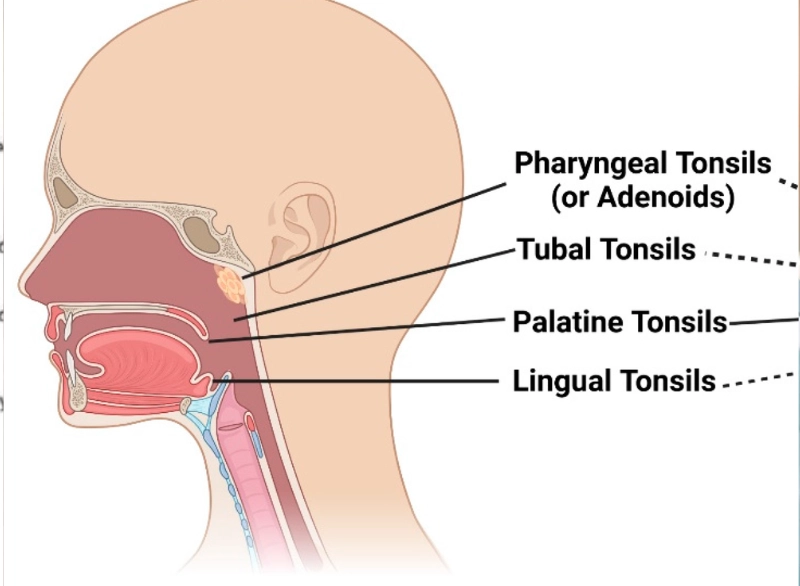

Adenoidectomy is the surgical removal of the adenoids—small lymphatic tissue located behind the nasal passage. When these become enlarged or infected frequently, they can block airways, cause snoring, breathing problems, and persistent ear or sinus infections.